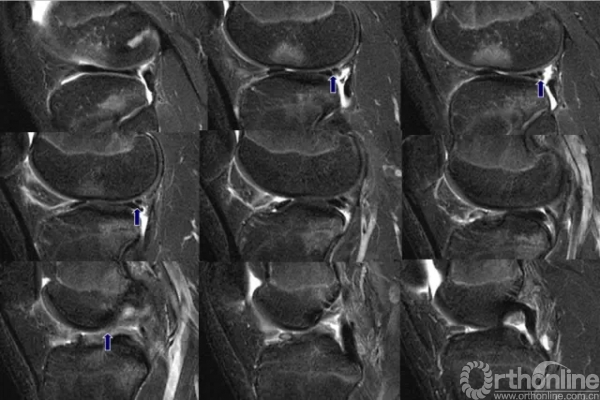

磁共振半月板撕裂图片、供球友们参考。|运动聊伤 -

半月板撕裂的分类及MR的诊断要点

半月板撕裂的分类及MR的诊断要点 | 骨科在线